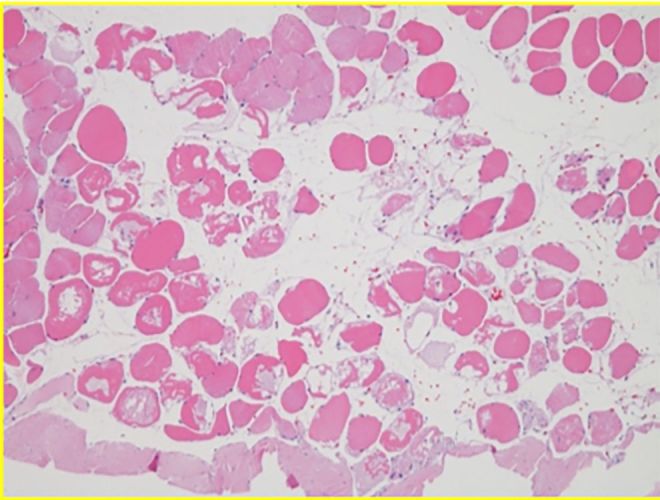

Histology

Histological Sections • Cellular Architecture • Tissue Response